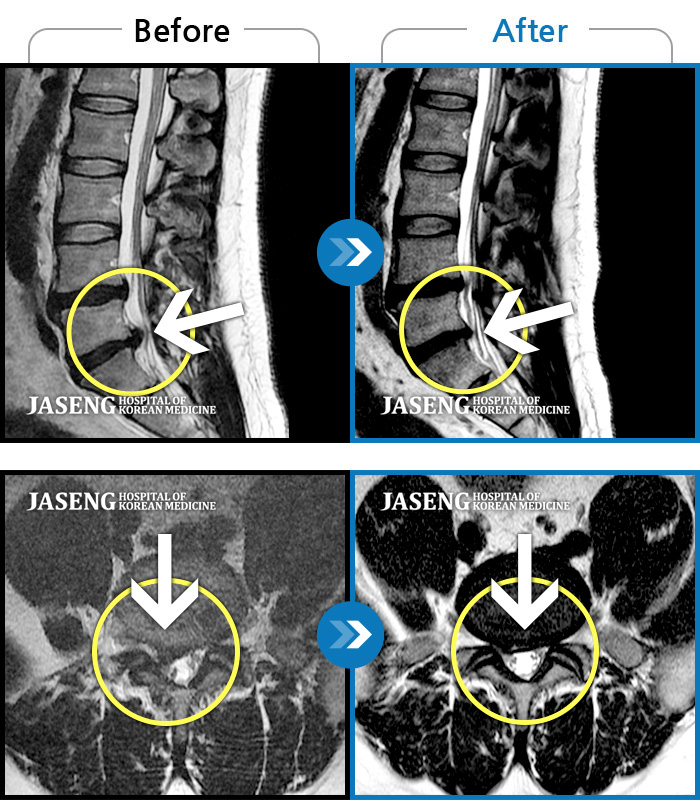

자생 비수술 한방통합치료 후

터진디스크가 흡수된 모습

Before

터진디스크 한방통합치료 전

After

터진디스크 한방통합치료 후

비수술 치료만으로

터진 디스크 흡수

튀어나온 디스크 대비,

터진 디스크 치료 효과 우수

디스크 흘러내린 정도가

심할수록 흡수 가능성 증가

치료 후 장기추적관찰 결과,

환자 90% 이상 치료 만족